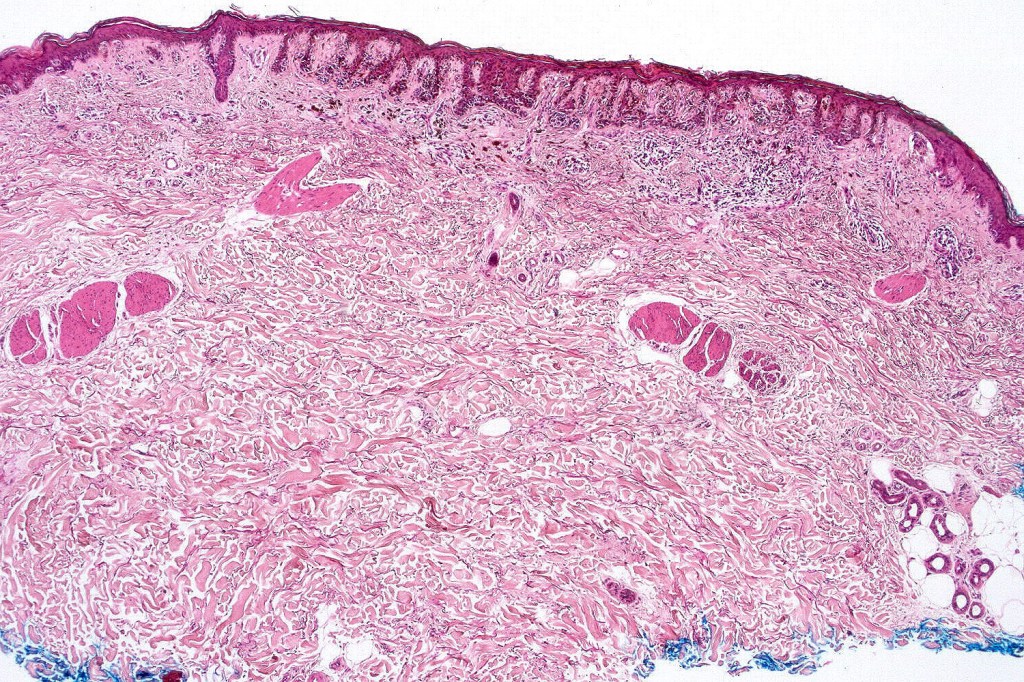

•Host response- eosinophilic & lamellar fibroplasia, increased vascularity, lymphocytic infiltration & pigment incontinence

•In compound lesions, the nest size should be smaller than the junctional ones and the degree of atypia the same or less

•No dermal mitoses